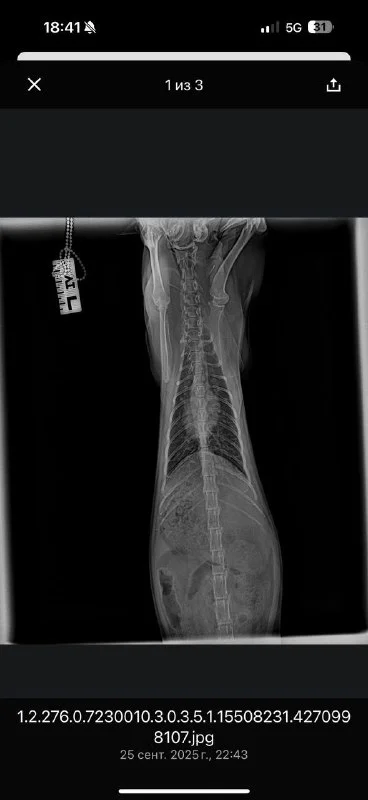

Вчера я ее забрала домой, операция прошла успешно, она уже пытается вставать на все 4 лапы, но у нее действительно есть проблемы с головой, непонятно что со зрением и двигается она только вокруг своей оси, ну ладно с этим потом буду разбираться. Публикую наконец фото рентгена, новый счет (который финально оказался меньше!) ресит с указанием оплаты и баланса.

Рентген ужас,руки в кадре, укладка жуть

Рентген это тот что в имерженси делали это мои руки 🤦🏼♀️ у них бардак конечно, хорошие люди, Михалис хороший хирург, но всегда толпа народа все носятся, но я к ним продолжаю ходить они меня знают и живу рядом